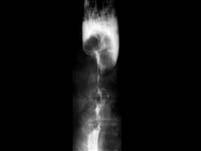

问题 下列哪项食管吞钡的X线表现,显示食管瘤已发展到晚期()

选项 A.食管管腔狭窄、梗阻 B.小龛影 C.局限性管壁僵硬 D.局限、小的充盈缺损 E.局限性粘膜皱襞增粗和断裂

答案 A